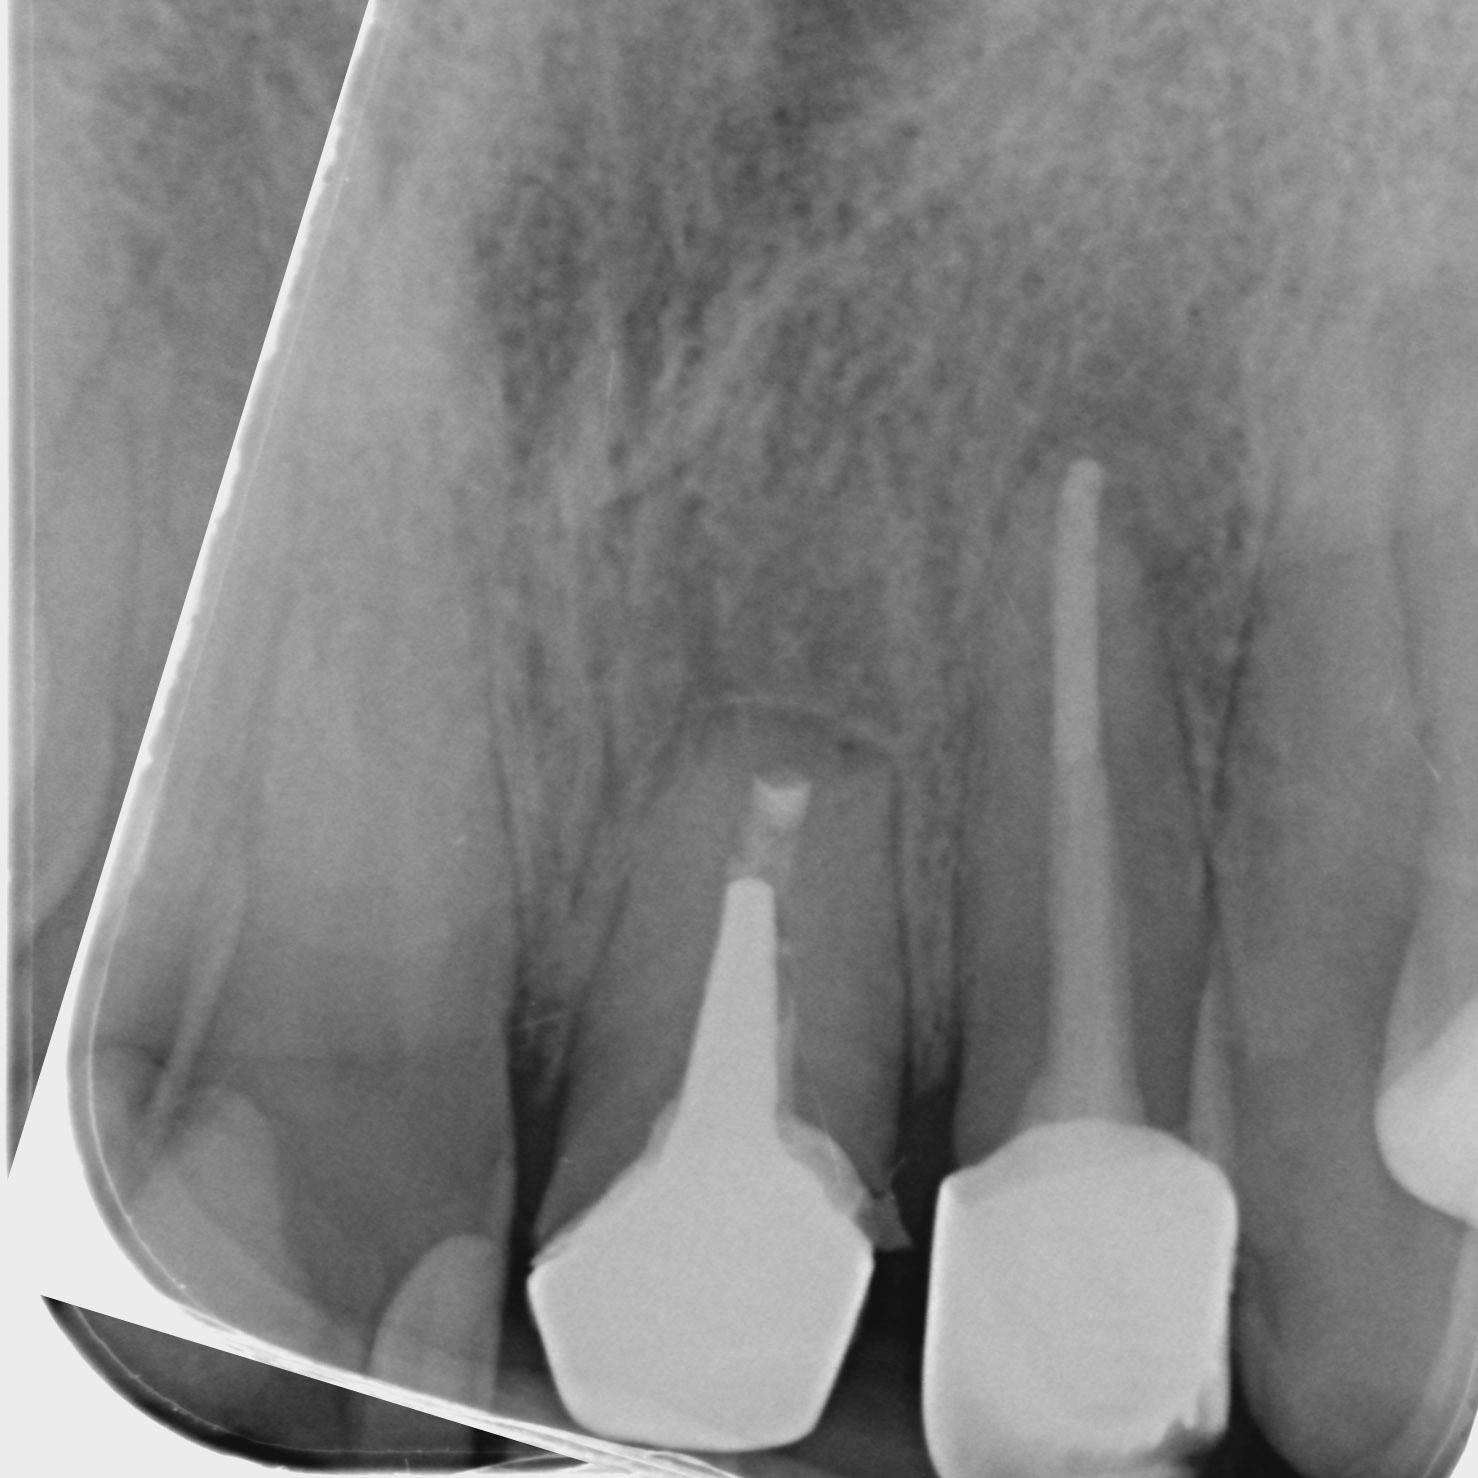

Mikroskopická endodoncie

Komplikovaný kanálkový systém nemusí znamenat kompromis. Rádi za Vás takové případy ošetříme, či provedeme reendodoncii.